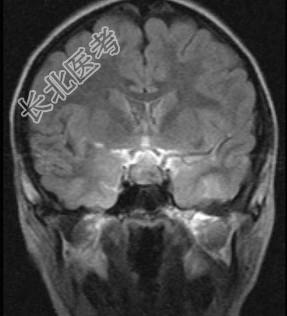

- 多项选择题鞍区肿瘤(如图所示)的临床表现包括 ( )

A、内分泌功能障碍

D、视力、视野障碍

E、原发性视乳头萎缩